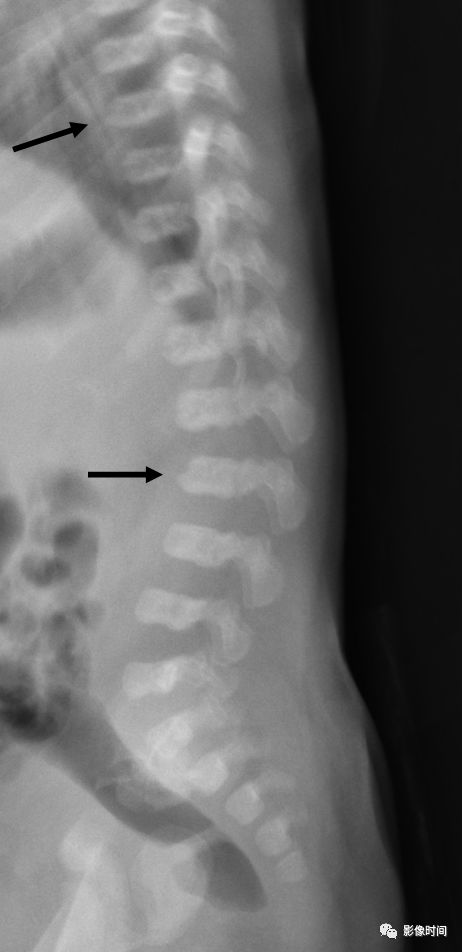

22亮角征

亮角征(shiny corner sign),又称 Romanus 病灶(Romanus lesion)

亮角征指的是在侧位片或者 CT、MRI 矢状位图像上,椎体的上角或者下角密度(或信号)增高(黑箭),「发亮」,故而得名。本征象主要见于血清阴性脊柱关节病(尤其是强直性脊柱炎)。在 X 线片上此征象的出现是由于于椎体角部炎症性侵蚀而导致的反应性骨质硬化。在磁共振上,活动性疾病表现为 T1WI 低,T2WI 压脂高信号,疾病进程后期则因为脂肪骨髓变性而呈现 T1WI、T2WI 双高信号。

典型病例

病例 1,53 岁男性,强直性脊柱炎。侧位 X 线片示部分椎体前上角密度增高,呈亮角征(黑箭)。

病例 2,男性,38 岁。强直性脊柱炎。A. 矢状位 T1WI 示胸腰段多发椎体角部信号增高(白箭),呈亮角征;B.STIR 序列亦呈稍高信号(白箭, 提示有活动性炎症)。

引用自:https://radiopaedia.org/articles/shiny-corner-sign-ankylosing-spondylitis